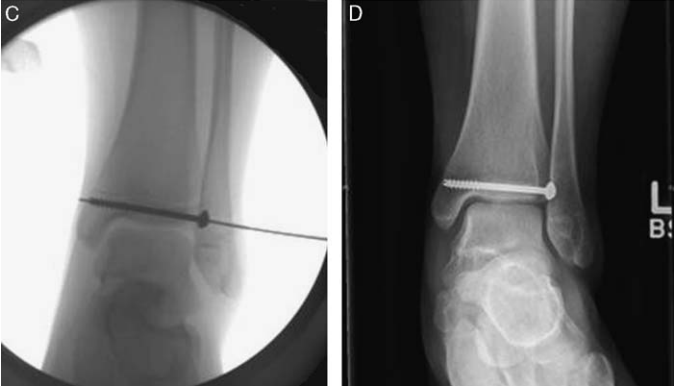

图源:DOI: 10.1302/2058-5241.6.200042.